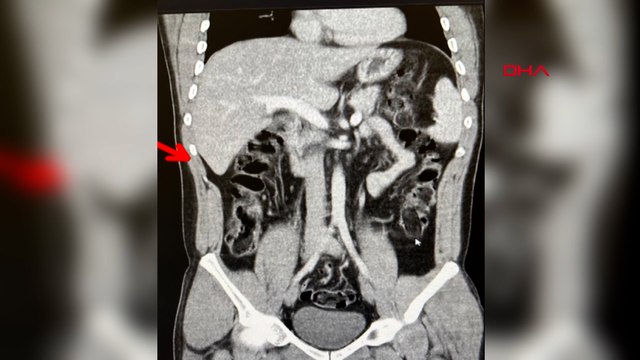

Erzurum'da düzenlenen operasyonda, vücutlarından 6 kilo 955 gram ağırlığında 683 kapsül uyuşturucu çıkan İran uyruklu 5 zanlı tutuklandı. İl Emniyet Müdürlüğü Narkotik Suçlarla Mücadele Şubesi ekipleri, batı illerine uyuşturucu nakli yapan kişi ve araçlara yönelik çalışmaları kapsamında Erzurum-Erzincan kara yolunda uygulama gerçekleştirdi. Bu çerçevede bir otomobilde durumlarından şüphelenilen ve araçlarında yapılan aramada çantalarından tokluk hissi veren ve bağırsak temizleyici ilaçlar çıkan İran uyruklu Mehdı B, Mılad F. ve Sıraus G. gözaltına alınarak hastaneye götürüldü.Çekilen röntgen filmlerinde şüphelilerin vücutlarında 62 kapsül eroin ve 210 kapsül afyon sakızı olduğu tespit edildi.